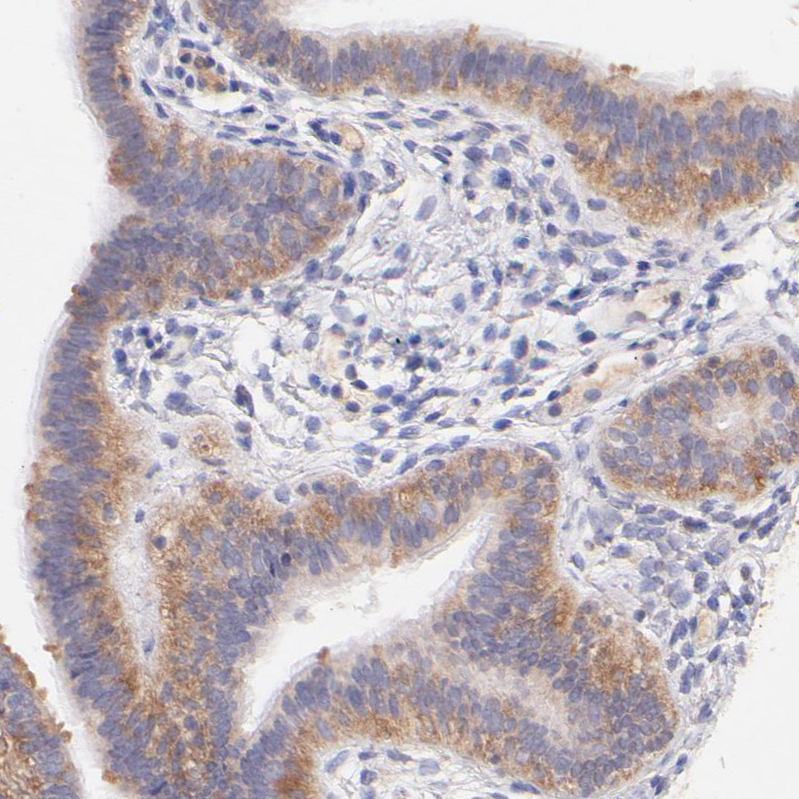

Immunohistochemical staining of human Fallopian tube shows moderate cytoplasmic positivity in glandular cells.